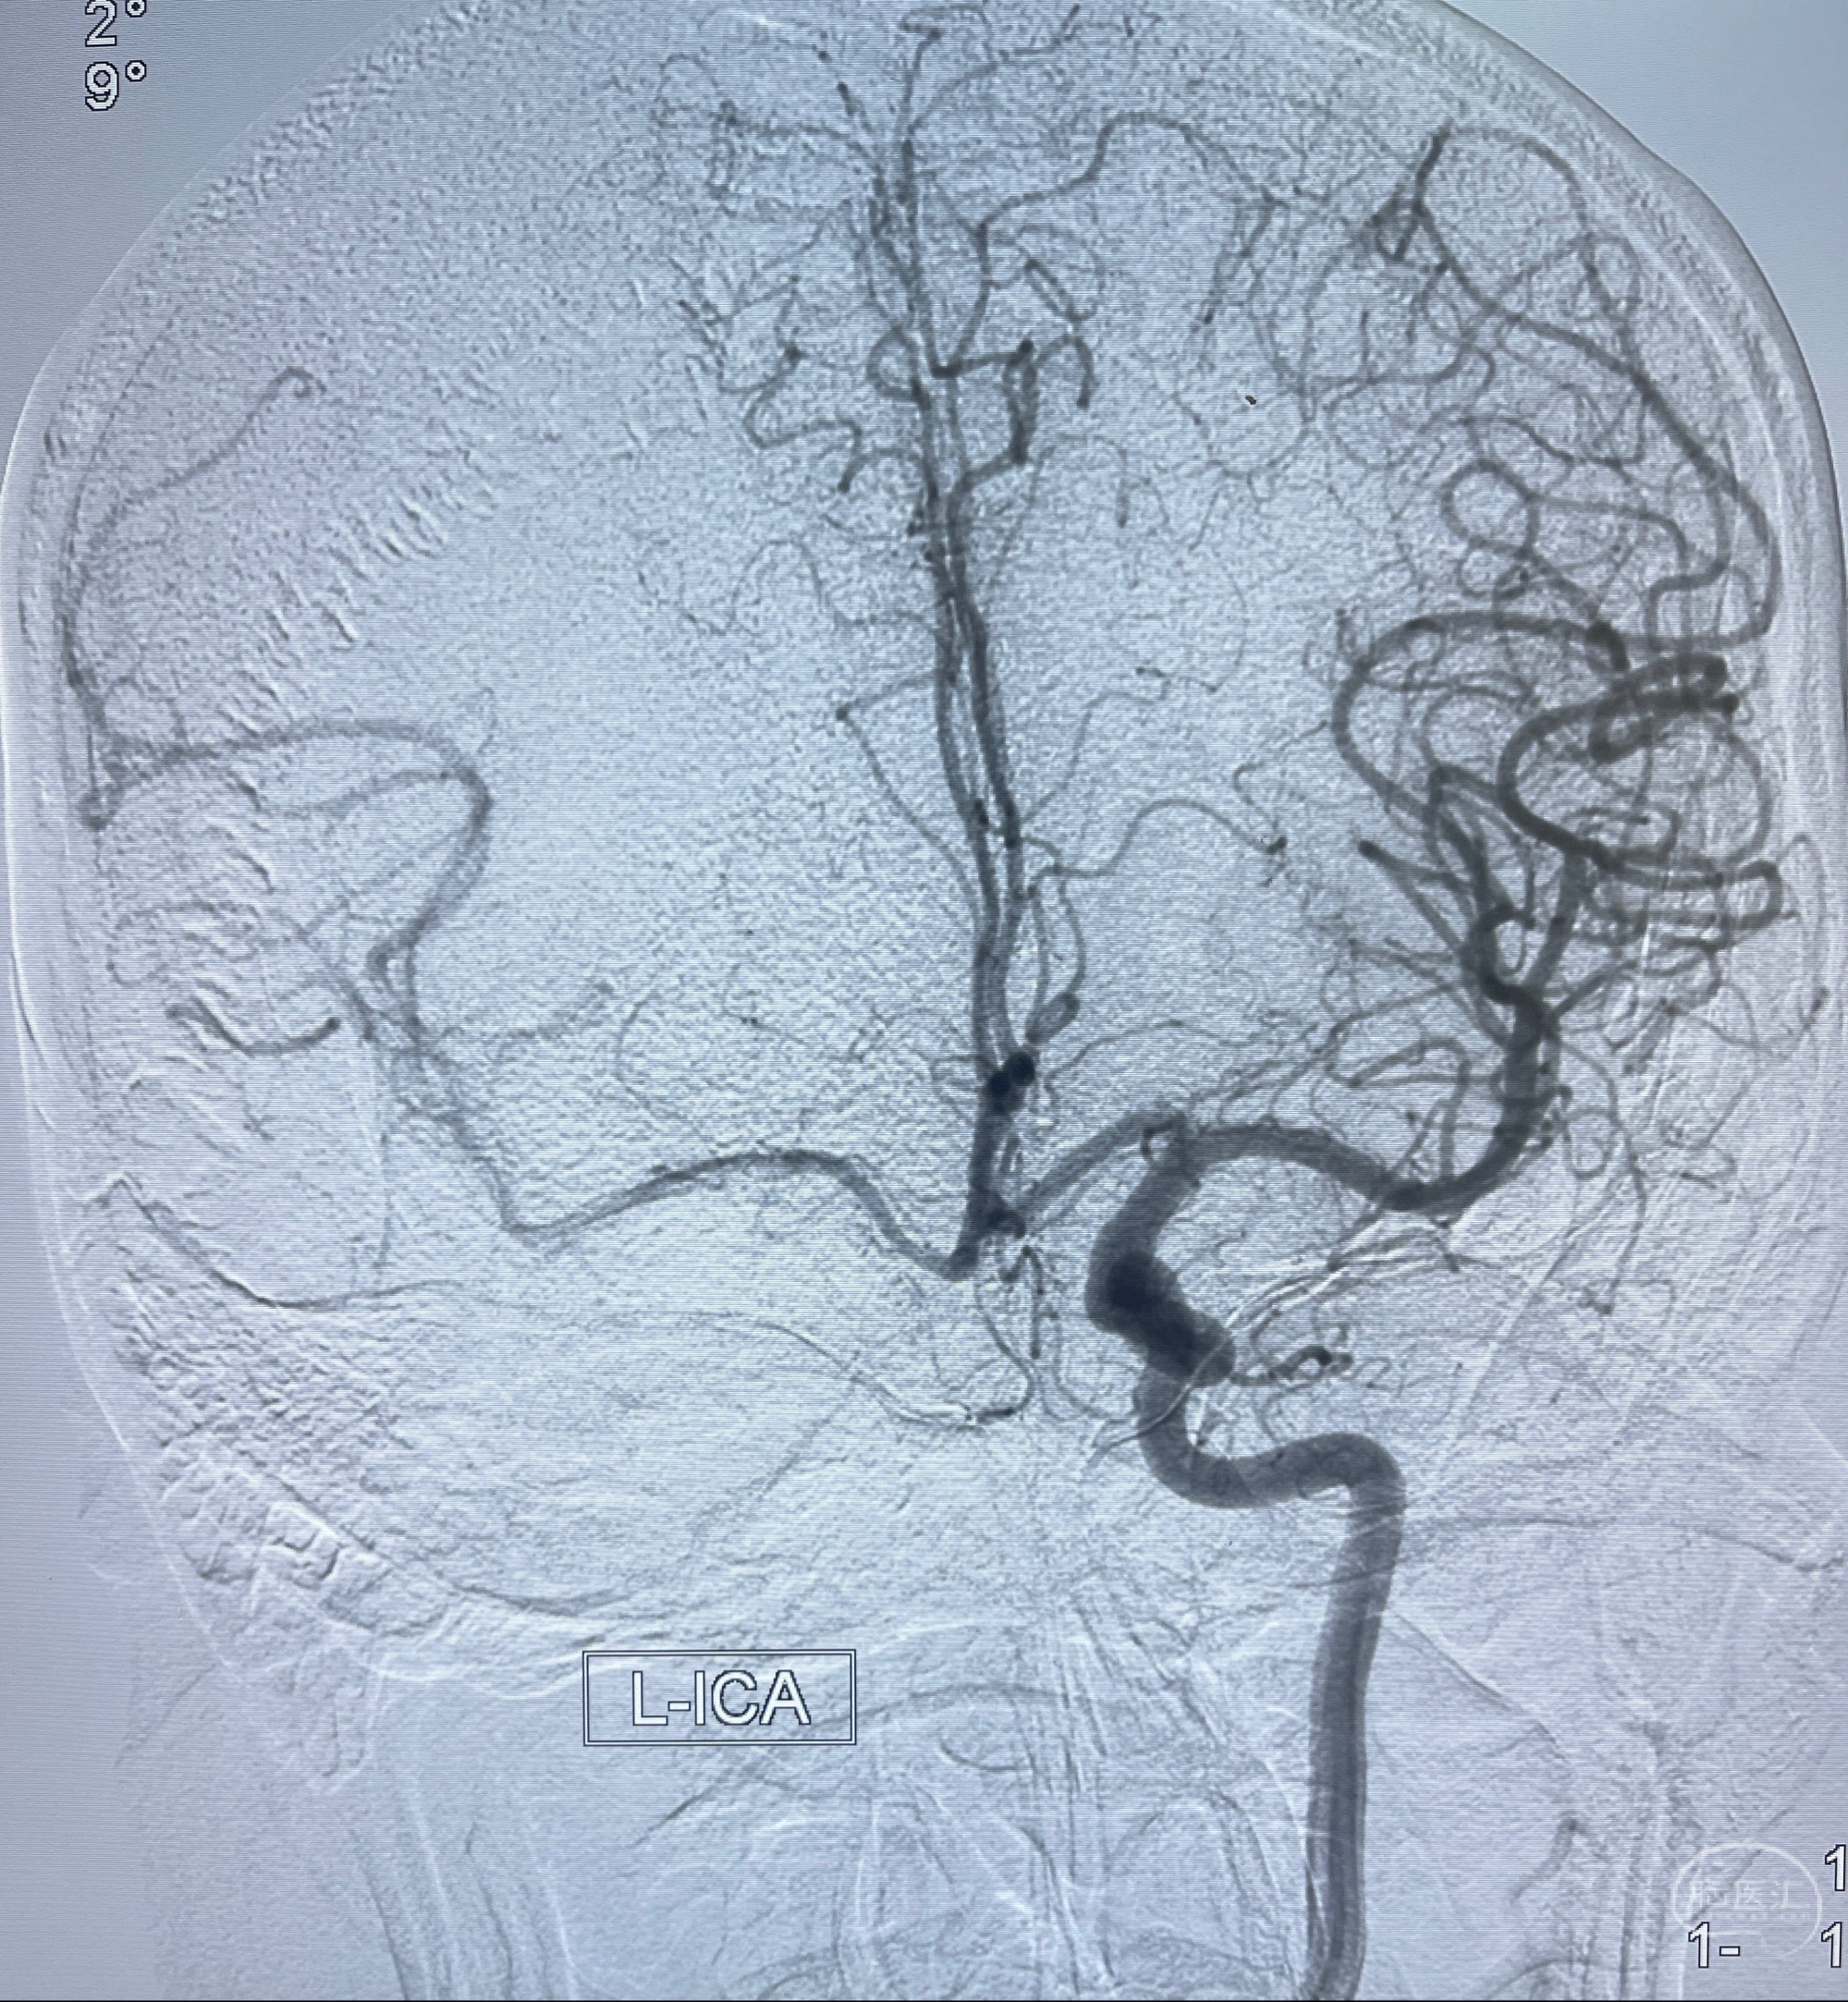

2023.07.25 泰州市人民医院查头颅CTA提示右侧C6段瘤样突起,建议DSA检查;

CTA示:右侧颈内动脉C6段见指向下方的突起,余左侧颈内动脉、双侧椎动脉、大脑前动脉、大脑中动脉、大脑后动脉及基底动脉走形正常,未见明显扩张及狭窄,局部未见明显瘤样扩张。

2023-07-27全脑血管造影:双侧颈内动脉眼动脉段动脉瘤,右侧较大